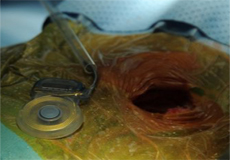

من جهة أخرى ذكر الدكتور حازم العيد استشاري زراعة القوقعة في مدينة الملك عبد العزيز الطبية بالرياض أن هذه القوقعة متطورة جداً وتعتبر الأصغر حجماً والأخف وزناً في العالم حيث لا يزيد سمكها عن مليمترات بسيطة ولا يتعدى وزنها السبعة غرامات وهي مصنوعة كليا من التيتانيوم. ووصف الدكتور العيد هذه المميزات بأنها مهمة جداً خاصة للأطفال الأصغر عمراَ حيث إنها لا تحتاج سوى جرح بسيط ووقت قصير للعملية.